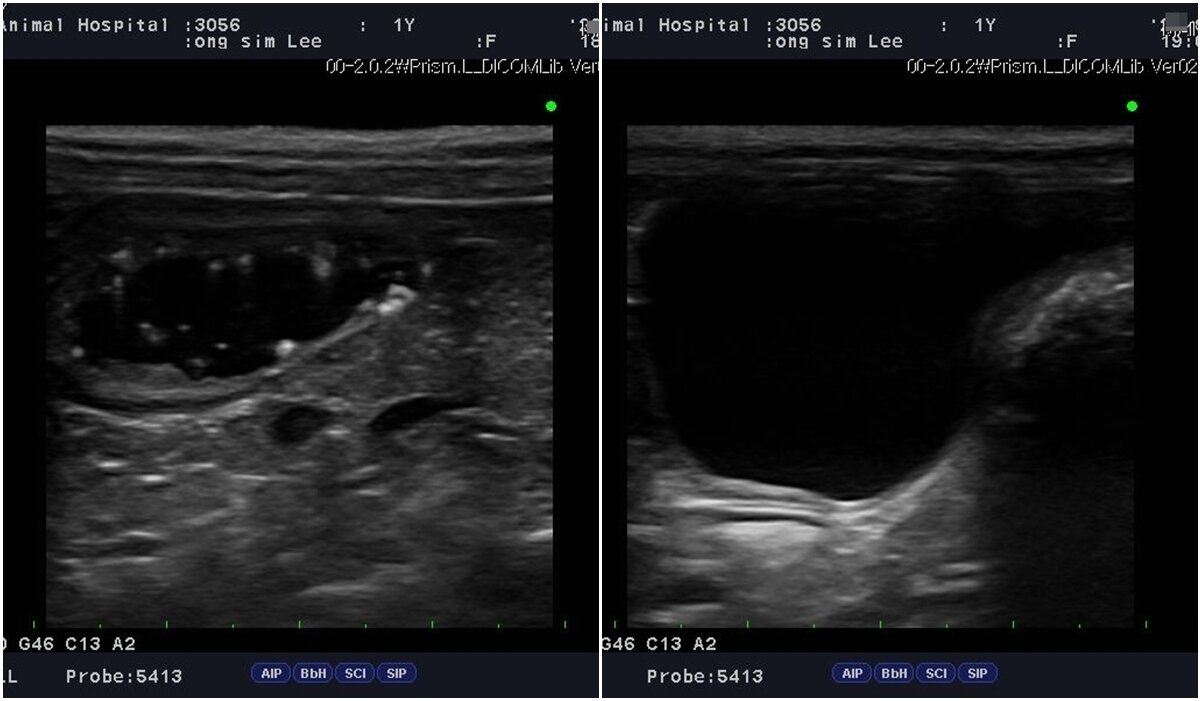

본문 이미지 - 1살 반려견이 건강검진을 통해 방광 슬러지가 확인됐지만 조기 발견 덕에 한 달 만에 회복해 결석을 예방할 수 있었다. 건강검진 당시 초음파 이미지(왼쪽)와 한 달 치료 후 슬러지가 사라진 모습(메인동물병원 제공) ⓒ 뉴스1

1살 반려견이 건강검진을 통해 방광 슬러지가 확인됐지만 조기 발견 덕에 한 달 만에 회복해 결석을 예방할 수 있었다. 건강검진 당시 초음파 이미지(왼쪽)와 한 달 치료 후 슬러지가 사라진 모습(메인동물병원 제공) ⓒ 뉴스1